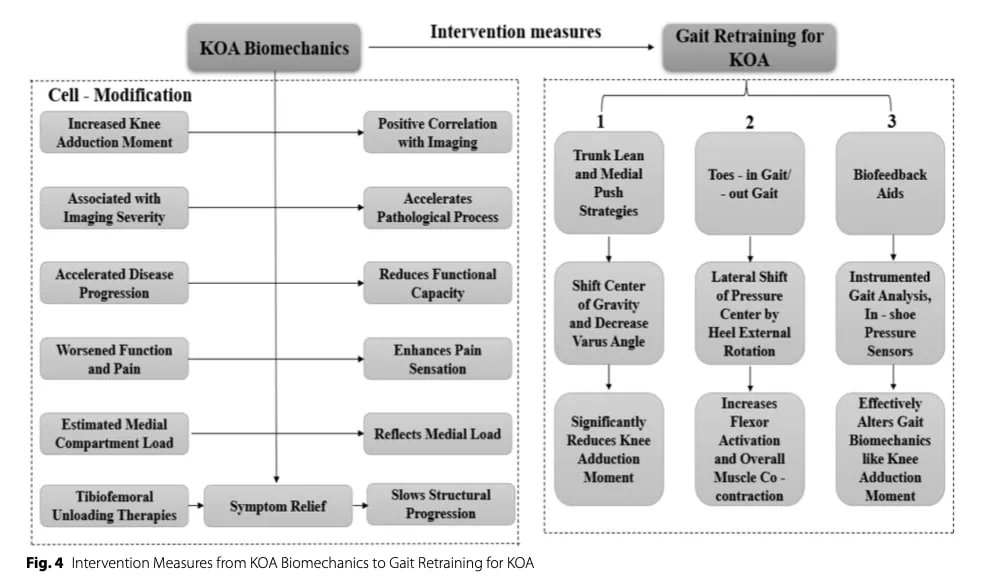

生物力学方法

膝关节负荷分布的改变会增加关节软骨的机制压力,导致症状进展。 因此,旨在优化下肢对齐和减少关节过度负荷的干预措施可改善疼痛和功能。 值得注意的是,已发现步态期间膝关节内收力矩增加与疼痛严重程度、疾病进展和内侧间室退化之间存在关联。

步态再训练

步态再训练策略旨在减少膝关节内收力矩,而膝关节内收力矩与膝关节内侧骨关节炎的严重程度和进展有关。 以生物反馈为基础的干预措施(如鞋内压力传感器)已显示出改变步态机制的有效性,而使用镜子进行视觉反馈则可能提供一种低成本的替代方法。

包括躯干倾斜、膝关节内侧推力("内侧推")、缩短步长和趾外翻步态在内的特异性策略已被证明可通过改变下肢对齐和负荷模式来减少膝关节内收力矩。 然而,这些策略可能会增加相邻关节(髋关节或踝关节)的负荷或增加肌肉的共收缩,从而可能会增加压迫力和症状。